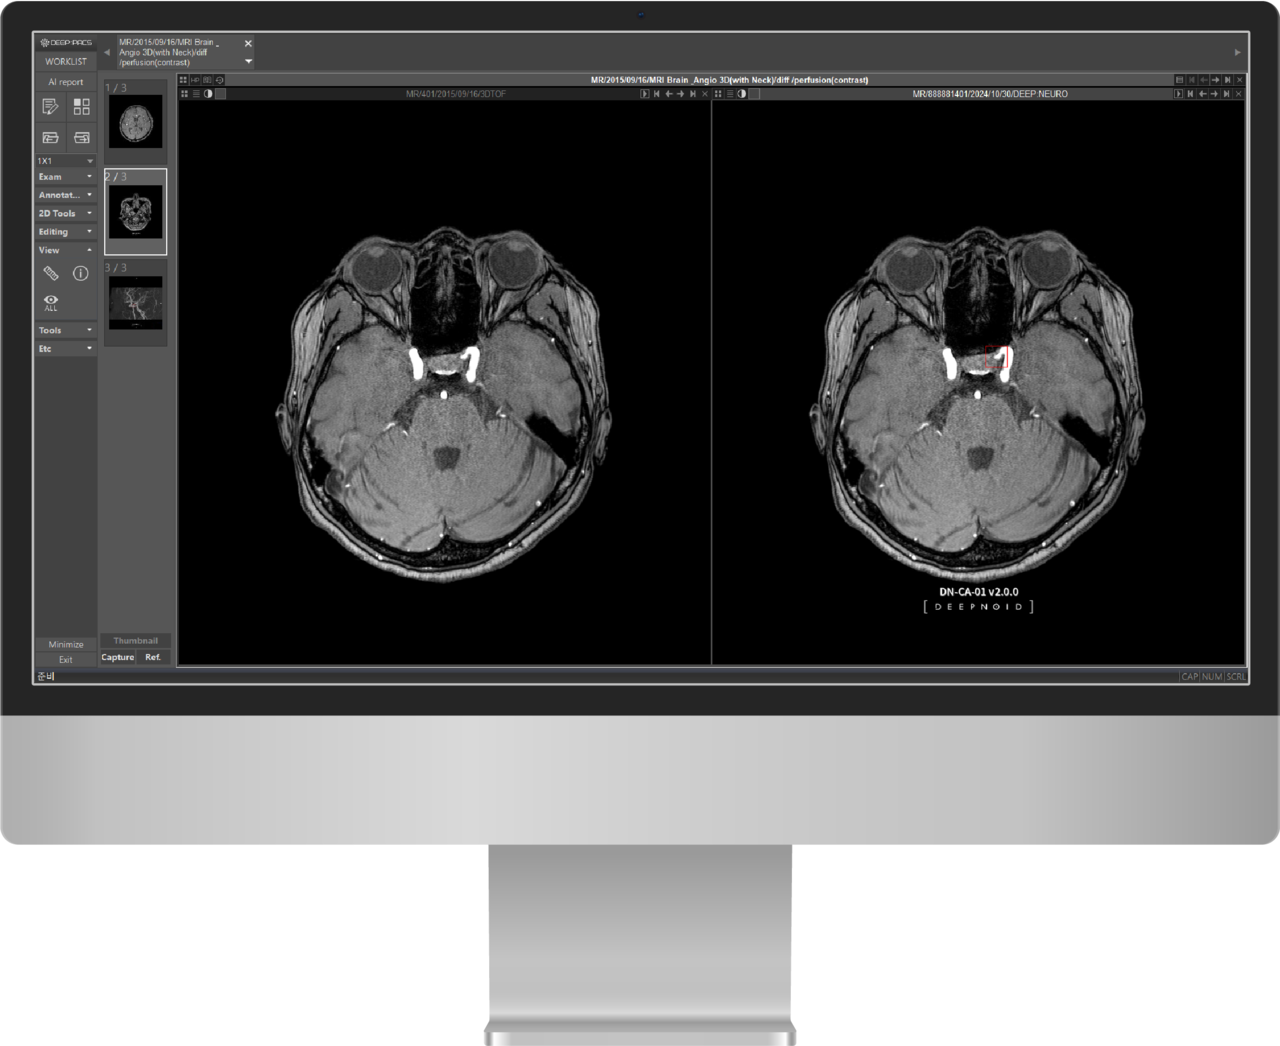

의료 인공지능(AI) 전문 딥노이드(대표 최우식)는 뇌동맥류 진단보조 AI솔루션 ‘딥뉴로’가 비급여 코드를 획득했다고 1일 밝혔다.

뇌 MRA 검사 수요도 매출 견인에 도움을 줄 것으로 판단하고 있다. 뇌동맥류가 파열될 경우 장애나 후유증, 심할 경우사망까지 이르게 되지만 반드시 수술로 직결되는 것은 아니다. 케이스에 따라 추적관찰을 통해 관리하거나 비수술적 치료를 진행할 수도 있다. 환자는 뇌동맥류의 상태 변화나 치료 효과를 확인하기 위해 주기적으로 MRA 검사를 받게 된다는 설명이다.